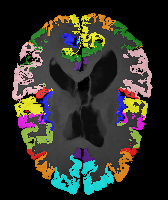

Results: All trained networks are evaluated using Dice overlap scores between predictions and the manual segmentations for the segmentation network, or between the warped moving segmentations and the target segmentations for the registration network. Tabs. 1 and 2 show results for the knee and brain MRI experiments respectively in Dice scores (%). Fig. 2 shows examples of knee MRI registrations and brain MRI segmentations.

Brain results: Dice scores for segmentation and registration increase by about 2.6 and 3.5 respectively for the cortical structures of the brain MRIs.

One-shot learning: In the one-shot experiments on both datasets, reasonable segmentation performance is achieved; moreover, DA increases the Dice score over unsupervised registration by about 2.7 and 1.8 on the knee and brain data respectively. This demonstrates the effectiveness of our framework for one-shot learning.

Qualitative results: DA achieves more anatomically consistent registrations than the mono-networks on the knee (Fig. 2) and Brain MRI samples (see supplementary material).